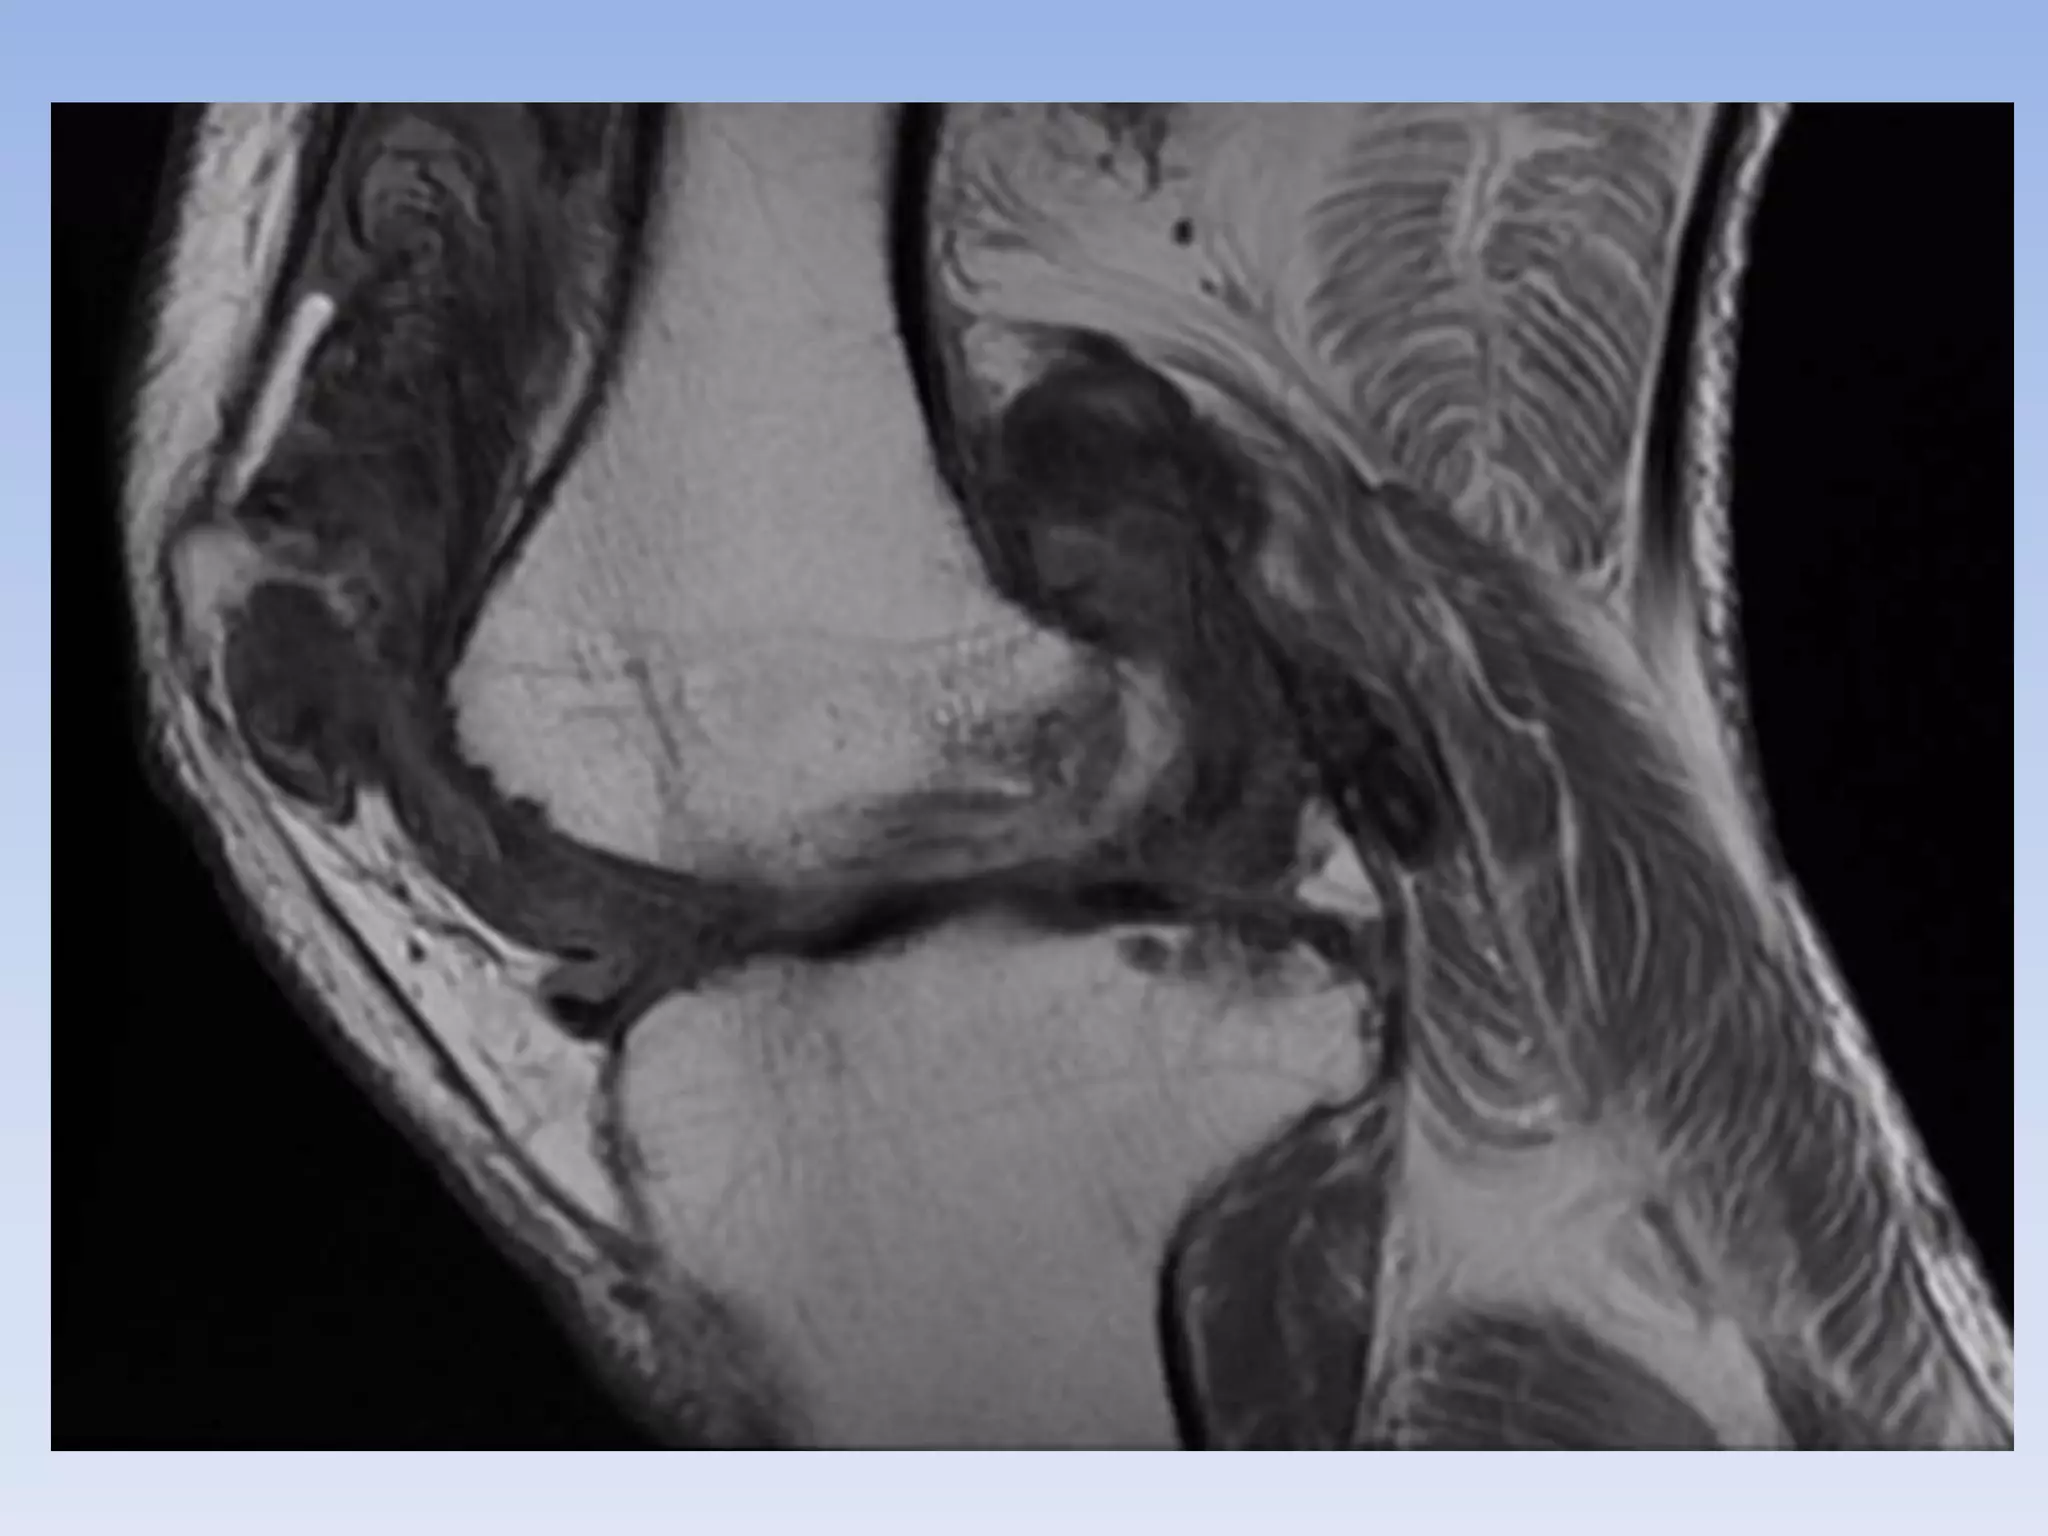

Histology

• PVNS lesions on histology demonstrate

synovial cell proliferation,

xanthomatous cell accumulation,

hemosiderin deposition, and the

presence of multinucleated giant cells

Histology • PVNSlesions on histology demonstrate synovial cell proliferation, xanthomatous cell accumulation, hemosiderin deposition, and the presence of multinucleated giant cells